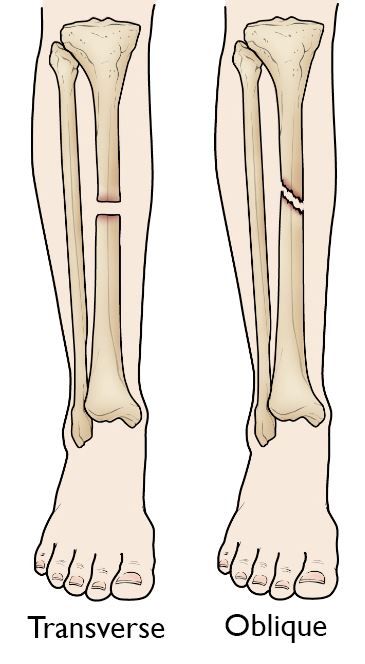

• Transverse fracture: In this type of fracture, the break is a straight horizontal line going across the tibial shaft.

• Oblique fracture: This type of fracture has an angled line across the shaft.

Transverse and oblique tibial shaft fractures

(Left) A transverse fracture has a horizontal line across the shaft. (Right) An oblique fracture has an angled line across the shaft.